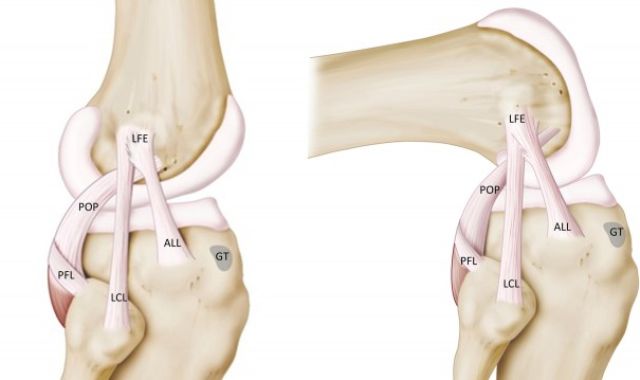

Antero-Lateral Ligament (ALL) Augmentation

The anterolateral ligament(ALL) is a ligament on the lateral aspect of the human...